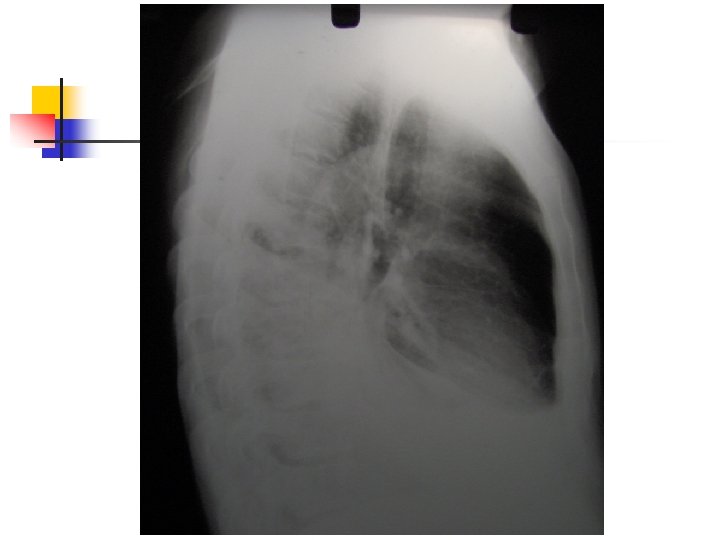

Aproximación diagnóstica: Radiología n n n 250 ml son necesarios para provocar alteraciones radiológicas. Primer signo: Borramiento del SCD Damoisseau. Desviación de estructuras. Derrame tabicado.